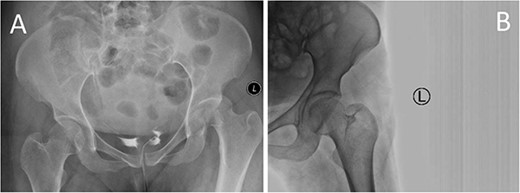

A medically free 42-year female presented to our institute as a life-saving case from a different hospital as she was a victim of unrestrained road traffic accident 2 days prior to presentation. Upon assessment in the emergency department (ER), she was conscious and oriented, and was found to have bilateral lung contusion, and multiple fractures of ribs. She also had a left sided vertical femoral head fracture dislocation comprising around 40% of the femoral head (Fig. 1). Closed reduction under conscious sedation was done in the ER, which was successful based on post-reduction imaging studies (Fig. 2). Her chest injuries were treated with chest tube and observation for 10 days. During that time, discussion was made with the patient regarding her situation and conservative management was chosen by way of bed rest and continuation of skeletal traction for 4 weeks with serial radiographs in the hospital on a weekly basis after clearance of her chest injuries. Skeletal traction was discontinued and she was advised to continue bed to wheelchair mobilization for an additional 2 weeks. After 6-weeks from the injury, a Computed Tomography (CT) was done to the patient and revealed signs of fracture healing (Fig. 3). At 3-years after the injury, she was found to have full painless range of motion of the affected hip and has resumed her activity of daily living without any complaints and the images showed a symmetrical joint space of the hips (Fig. 4).

CT scan of the pelvis showing axial (A) and coronal (B) cuts at 6-week post-injury showing signs of healing of the left fractured femoral head with a concentric hip joint.

Yoon et al. proposed that small or comminuted Pipkin I require surgical excision, whereas large fragments typically require anatomical fragment reduction and fixation [10]. What made us consider offering conservative treatment is that the fragment was anatomically reduced in postreduction computed tomography (CT) scan. Another reason that could have helped at maintaining the reduction is the vertical nature of the fracture, whereas if it was oblique or horizontal, shear forces produced by hip abductors would have displaced the fracture. Moreover, in the prereduction trauma CT, the fragment was found to be positioned well in the corresponding acetabulum likely restrained by iliopsoas, indirect head of the rectus femoris, and the capsule [11]. The patient was followed on a weekly basis with radiographs while on skeletal traction.